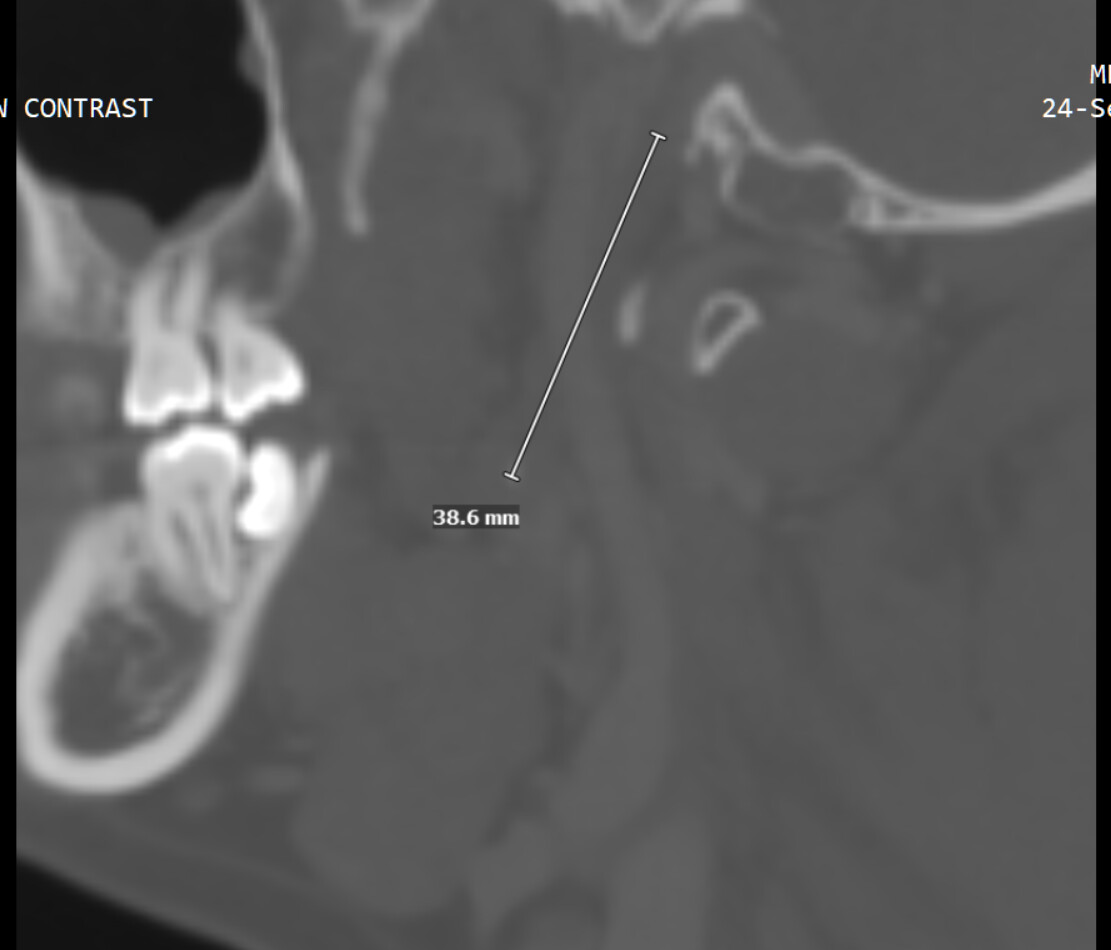

So in 2023 I went to Bellevue ENT, did a CT scan and got a diagnosis of possible Eagle Syndrome, because my styloid process is mildly elongated. But I hesitated to consider surgery because the symptom is not that bad. But in 2025 I finally decided to go to UW medical center and I am currently with Dr. Merati.

After the first visit, I tried speech therapy, which didn’t help at all. I just had my 2nd visit, and the doctor said there were 3 causes he knew of: 1) reflux from stomach (which I do have) 2) nerve damage 3) Eagle syndrome. He is not convinced it’s Eagle syndrome yet, because my left side is longer yet my problem is on the right side.